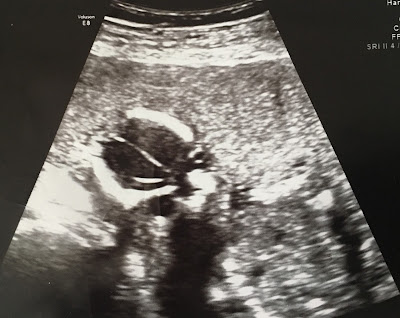

Throughout the Baby Chris project, we’ve been illustrating our articles with ultrasound images donated by Secular Pro-Life supporters. This week, we have two unusual photos to share. Mother Aimee explains:

I suffered from preterm premature rupture of membranes at 13 weeks and my pregnancy was deemed terminal for the duration of it. I received an ultrasound weekly until I delivered at 32 weeks so needless to say I have several ultrasound pictures to choose from. That being said, my fluid levels were very low (0-1.6cm) so they don’t look like a normal one. … I’ve been meaning to catalogue them anyway so I can show my daughter some day. This medically impossible child is currently rolling around in her crib refusing to nap.

![]() |

| 13 weeks and 6 days, with rupture of membranes |